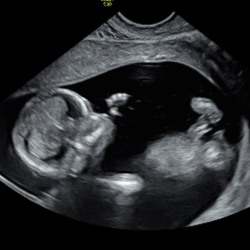

Zwanger

Zwangerschapskalender